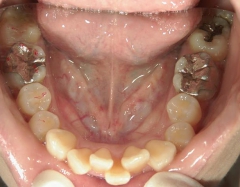

矯正歯科 治療前